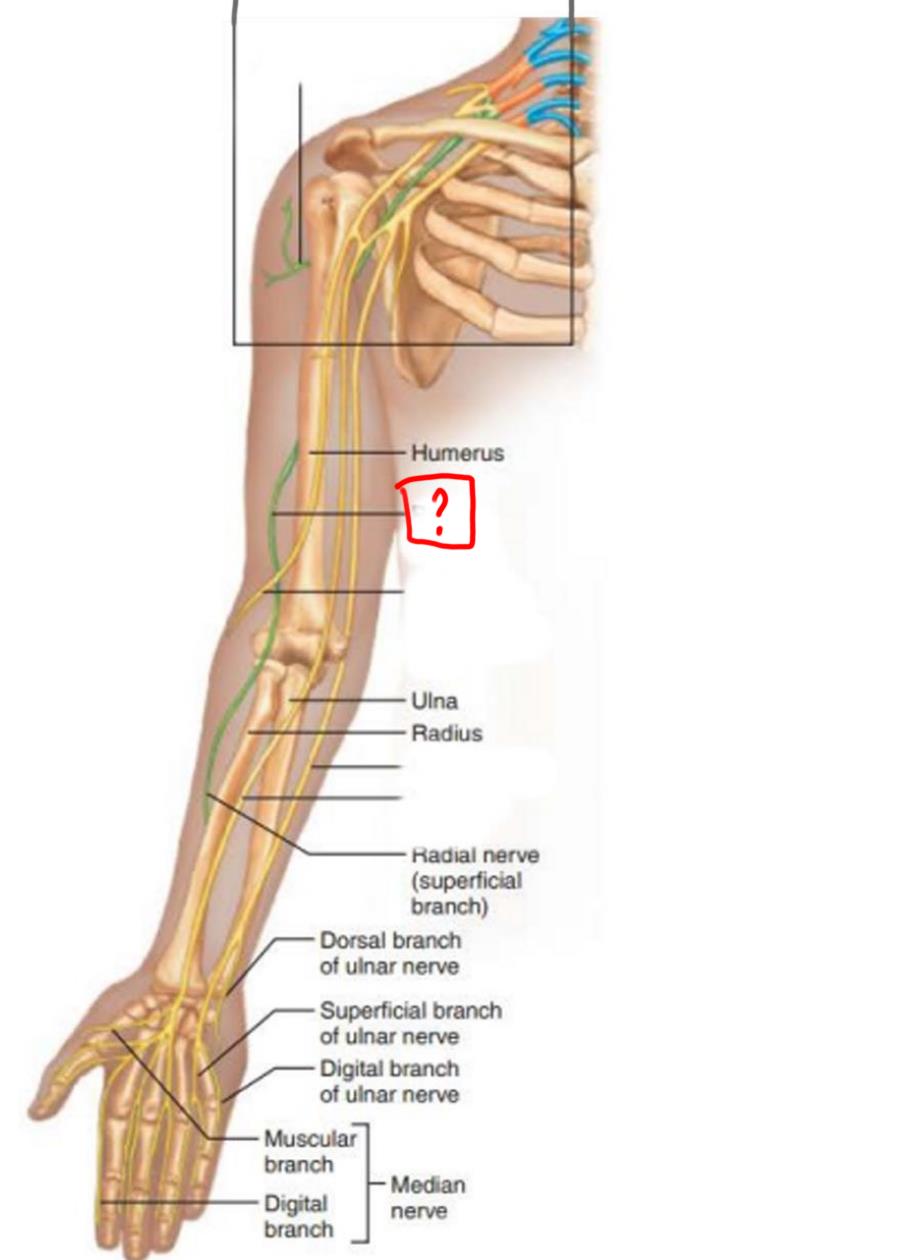

radial nerve

ulnar nerve

median nerve